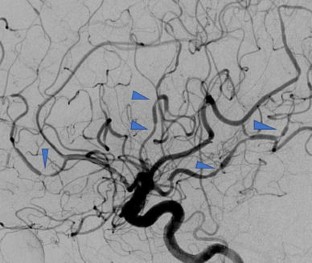

Reversible cerebral vasoconstriction syndrome: an important non-aneurysmal cause of thunderclap headaches and subarachnoid hemorrhage

Fig. 1